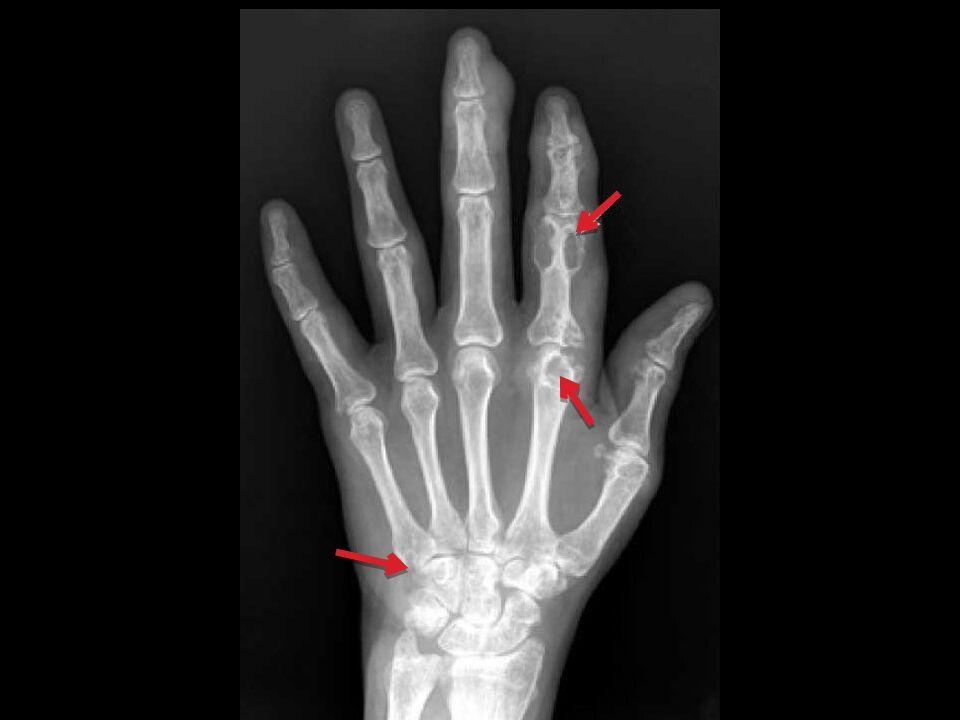

Суставной синдром, начинается как суставной криз (подагрическая атака). В 70% случаев поражается I-й плюснефаланговый сустав, т.е. развивается острый моноартрит. В 20% случаев дебют с поражением II – IV плюсне-фаланговых суставов, ГС, КС и, очень редко, суставов рук.

Приступы между атаками – от нескольких лет до 1 – 2 раза в год, укорачиваются по мере прогрессирования болезни. В межприступном периоде болей практически нет. В дальнейшем болезнь переходит в фазу хронического подагрического артрита с появлением постоянной боли, стойкой припухлости сустава и ограничением подвижности вследствие деструкции и вторичного остеоартроза. Суставной синдром становится более продолжительным, вовлекаются новые суставы.

Чаще всего ураты откладываются: периартикулярно в области МФС на разгибательных поверхностях; по наружному краю ушной раковины; в районе ахиллова сухожилия.